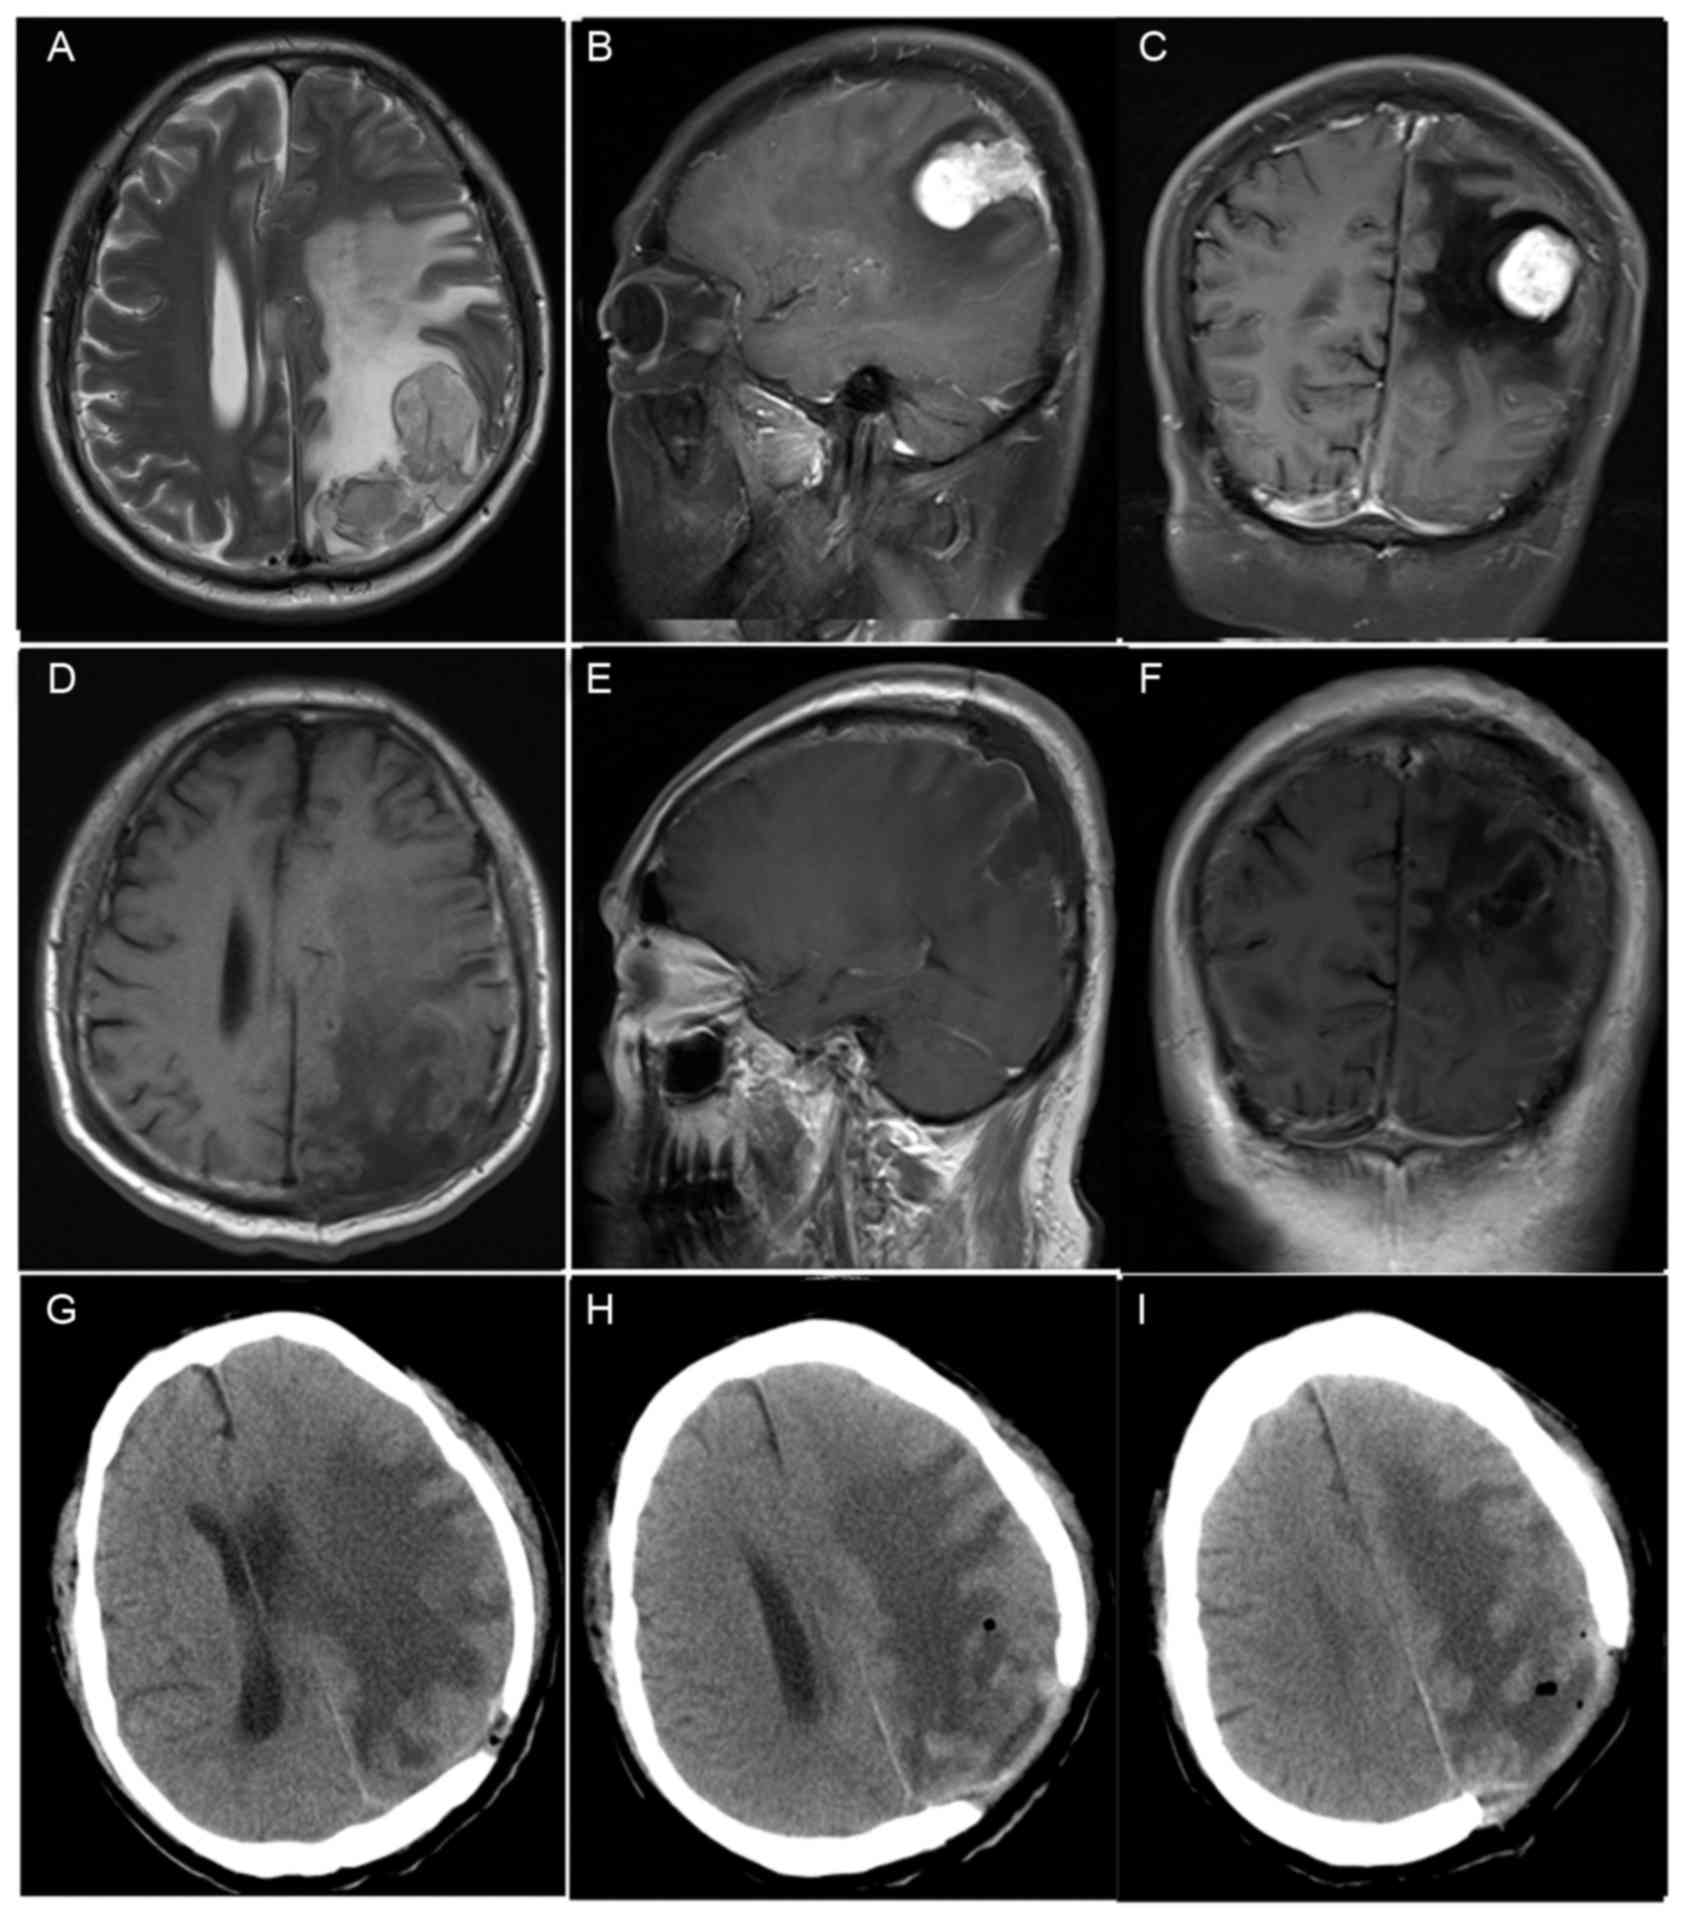

Preoperative MRI results were available in all 8 patients (Table II). The location of the tumors were as follows: Left frontal in two patients (cases 1 and 6); right frontal in two patients (cases 2 and 7); left parietal in two patients (cases 4 and 8; Fig. 1); right parietal in one patient (case 5); left anterior cranial fossa in one patient (case 3). Tumor size (maximum diameter on MRI) ranged between 2.5 and 5.4 cm (median, 3.4 cm). In total, 4 tumors were <3.0 cm in the longest dimension, 3 were 3.0–5.0 cm and 1 was >5.0 cm. MRI revealed well-circumscribed lesions and peritumoral edema was observed in 4 patients (cases 1, 2, 4, 6; Fig. 1). T1-weighted images revealed a hypointense signal in all eight patients. T2-weighted imaging showed a hyperintense signal in six patients and an isointense signal in two patients. Moderate enhancement was observed in three cases (cases 3, 7 and 8), and bright contrast enhancement was observed in five cases (cases 1, 2, 4, 5 and 6; Fig. 1).

Figure 1.

Case 4. (A) Magnetic resonance imaging of the brain shows hyperintense tumor on T2-weighted images. (B and C) Contrast-enhanced sagittal images and coronal images show a hyperintense tumor with marked enhancement in the left parietal. Peritumoral edema was evident. (D-F) Postoperative, contrast-enhanced axial, image and coronal images show that the lesion was totally resected. (G-I) A postoperative computed tomography image shows the left parietal bone defect. Case 4 was selected as complete patient data could be obtained.